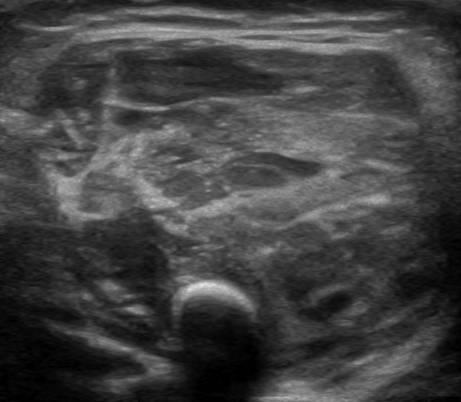

U xơ cơ

» Thông tin: Nữ giới – 3 tháng tuổi.

» Lâm sàng: Sưng vùng đùi.